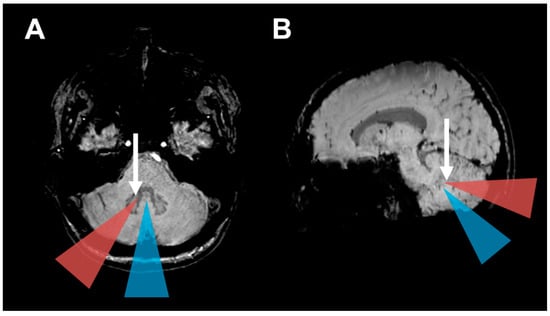

Figure 3.

HOD development based on operative approach: (A) Axial and (B) parasagittal magnetic resonance susceptibility-weighted images (SWI) illustrate the operative approaches investigated in this study. The blue triangles indicate midline approaches (telovelar and transvermian). The orange triangles indicate the paravermal trans-cerebellar operative corridor that frequently led to hypertrophic olivary degeneration in our cohort by injury to the dentate nucleus (Arrows).

In clinical routine, patients with posterior fossa tumors present with increased intracranial pressure and focal neurological deficits secondary to compression of the brainstem, cranial nerves or cerebellar tissue [41]. Furthermore, due to the tumor anatomy identifying DN is often complicated. Therefore, postoperative outcome parameters comprise of the immediate improvement of these symptoms derived mostly from the reduction of tumor mass effect. In contrast, the symptoms of HOD begin with a delay of months, progress slowly and are easily missed, complicating the allocation to the disease [5]. In concordance with literature, this study found the HOD on MRI with a delay of four months (median) after the contralateral surgical lesion [5,6,7]. Furthermore, most patients are usually not examined clinically in such a depth by neurosurgeons, so that the HOD symptoms may be missed. Some patients with HOD may thus be overlooked in clinical routine and the novel symptoms may mistakenly be attributed to tumor growth or novel pathology [5]. Impedingly, the clinical syndrome and especially palatal tremor is seldom diagnosed. Postoperative speech pathologist exam including fiberoptic endoscopic evaluation of swallowing (FEES) is considered a gold standard for detecting palatal tremor, but regular implementation is not yet universal amongst hospitals [14]. Furthermore, radiologists should also be sensitized for the imaging hallmarks of HOD. For a reliable detection of HOD, axial T2-weighted or FLAIR sequences with a slice thickness of at most 4 mm is recommendable. On standard MR-sequences such as T1-weighted imaging, preoperative identification of the DN can be challenging. However, in our experience the DN can be very well localized on susceptibility weighted imaging (SWI), which we therefore recommend for the neurosurgical planning (see Figure 3). In summary, since the HOD may be associated with a disabling clinical syndrome and therapeutic options are still unavailable, it must be primarily prevented [9,11,13]. Neurosurgeons therefore should consider sparing the DN in the surgical trajectory to prevent HOD occurrence whenever feasible. In some patients another operative trajectory is possible, whereas in other patients a fissure dissecting approach instead of a trans-cerebellar approach should be considered.